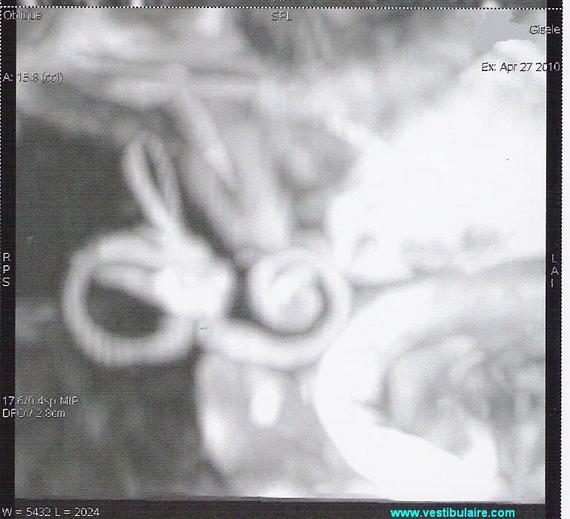

IRM du labyrinthe.

IRM de la zone labyrinthique.